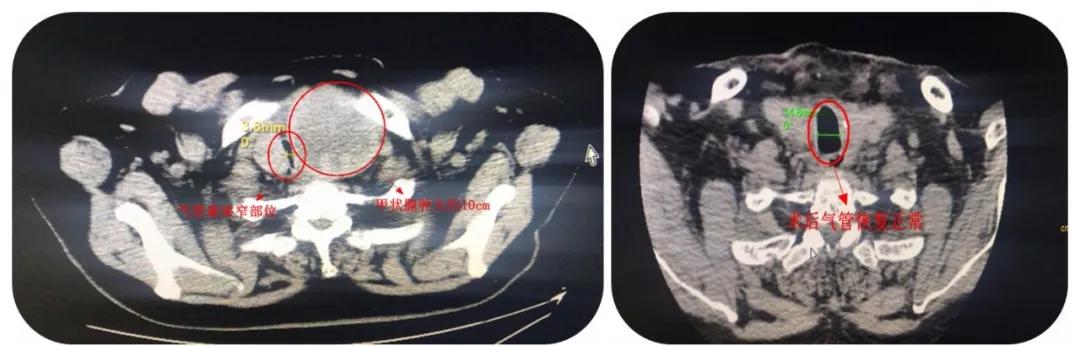

4年前,陈大爷发现自己颈部有个肿物,起初较小,陈大爷并没有在意,后颈部逐渐增大。近半个月,陈大爷在活动后总感觉胸闷,喘不上气,严重时会有呼吸困难,嘴唇发紫等症状。这可把家人吓坏了,辗转多家医院后,慕名来到漳州市第三医院,找到普外二科主任邹耀祥。邹主任详细询问病史并安排相关检查,CT结果显示:患者甲状腺肿大约10cm,且压迫气管,气管最狭窄部位只有4mm。患者需立即进行手术治疗,否则随时有窒息的风险...

术后患者恢复顺利,活动后胸闷气喘的症状明显改善,手术后复查颈部CT未见气管塌陷,没有神经及旁腺损失表现。

手术前(左图)后(右图)CT